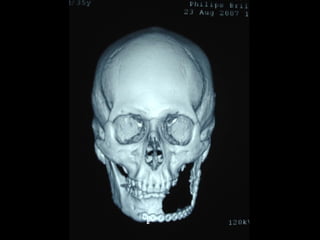

AmeloblastomaAmeloblastoma

Ameloblastoma

Neumólogo: Dr. Crescenciano González OlivaresNeumólogo: Dr. Crescenciano González Olivares

Trismus importante debido a queTrismus importante debido a que

El tumor ya rompió el hueso com-El tumor ya rompió el hueso com-

Pacto de la cara interna de laPacto de la cara interna de la

Mandíbula y empezó a tomar elMandíbula y empezó a tomar el

Músculo pterigoideo interno.Músculo pterigoideo interno.

Trismus importante debidoa queTrismus importante debido a que El tumor ya rompió el hueso com-El tumor ya rompió el hueso com- Pacto de la cara interna de laPacto de la cara interna de la Mandíbula y empezó a tomar elMandíbula y empezó a tomar el Músculo pterigoideo interno.Músculo pterigoideo interno.